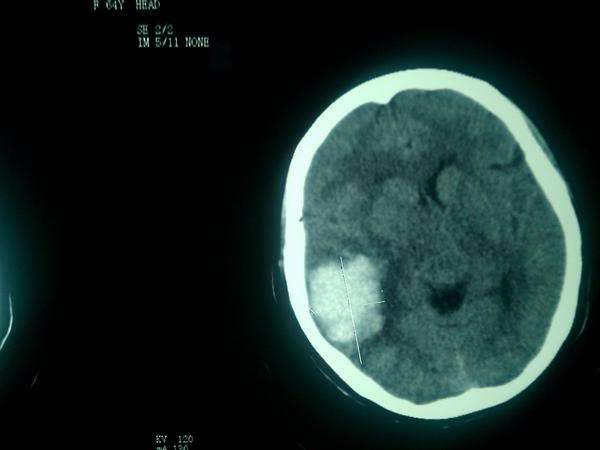

患者徐某某 ,女,55歲,家住濰坊市經(jīng)濟開發(fā)區(qū)馬家埠村。患者被家屬發(fā)現(xiàn)突然意識不清,呼之不應(yīng),惡心、嘔吐,右側(cè)肢體癱瘓。

家屬撥打120求救電話之后,由120救護車將患者接到市立醫(yī)院急診科。經(jīng)顱腦CT檢查后診斷為“腦出血”,主管醫(yī)師迅速對該患者進行了腦出血微創(chuàng)手術(shù),病情及時得以控制,病人轉(zhuǎn)危為安。手術(shù)12天后,病人能夠自行進食,獨立完成更衣、穿鞋等動作,自行走出病房并順利出院。事后,患者家屬送來錦旗表示感謝。

病例二

患者玄某某,女,90歲,濰坊市經(jīng)濟開發(fā)區(qū)邢石村人。2014年3月13日,患者突感眩暈,后重重摔倒在地,出現(xiàn)昏迷。家屬發(fā)現(xiàn)后立即撥打120求救,我院迅速派出救護車前往救治。

患者被接到醫(yī)院后,觀察出現(xiàn)呼吸不律且有呼吸短暫停止的跡象,瞳孔大小不等,情況十分危急。經(jīng)顱腦CT后診斷為“腦出血”。主管醫(yī)師當(dāng)即決定,為患者馬上進行腦出血微創(chuàng)手術(shù)。術(shù)后10天,患者意識清醒,身體指征正常,短暫休養(yǎng)后得以恢復(fù)出院。